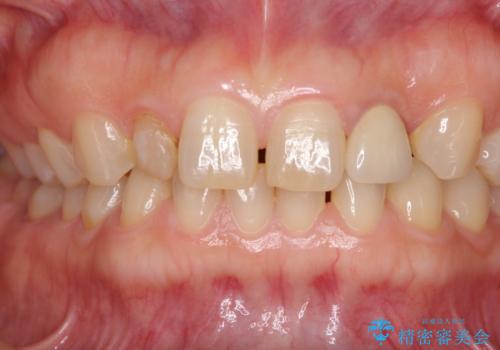

前歯の隙間や、周りの歯と色合いの違いなどはあまり気にしていらっしゃらなかったため、矮小歯の2歯を自然な大きさに仕上げました。

とても自然な歯が装着されたとのことで、患者様には大変満足していただきました。